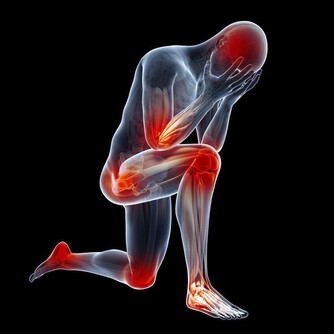

病毒感染患者會全身酸痛無力,但是膿性分泌物相對較少,而發燒、並且產生膿性分泌物為細菌感染的主要症狀,細菌感染也容易引起扁桃體發炎,細菌感染的傳染力弱於病毒感染,病毒感染的速度快,症狀明顯,而細菌感染則可急可緩。